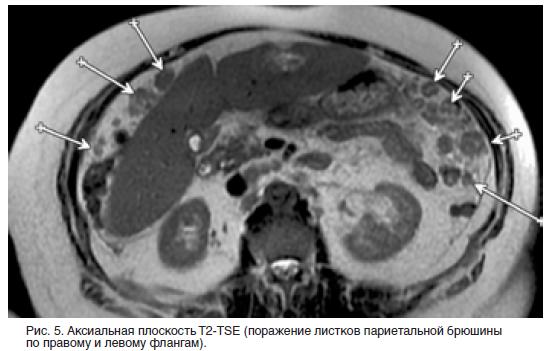

Канцероматоз таза

Канцероматоз таза 112 фото